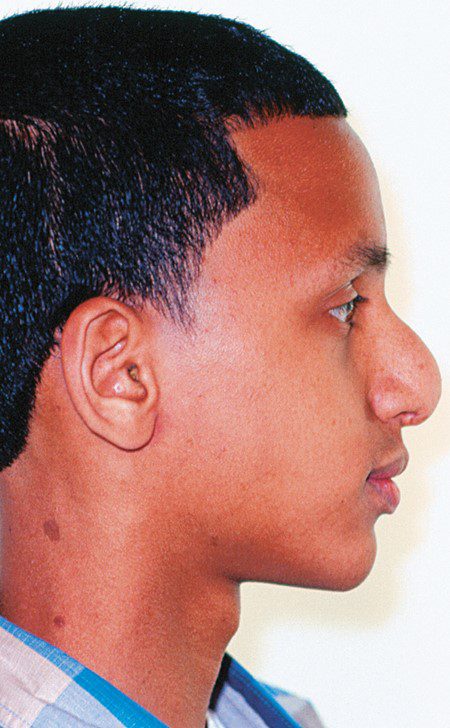

Thông thường, ba cấu trúc này duy trì một độ nhô (lồi) nhẹ, và độ nhô (lồi) này sẽ giảm đi trong tuổi dậy thì do sự phát triển không đồng đều của hai xương hàm. Trong giai đoạn bùng phát tăng trưởng dậy thì, hàm dưới có sự di chuyển ra trước nhiều hơn so với hàm trên. Cần lưu ý rằng khi kết thúc tăng trưởng, có sự khác biệt về giới tính trong độ nhô khuôn mặt, thường thì khuôn mặt nữ giới có xu hướng nhô hơn do xương cằm ít nhô ra hơn.

Sau khi đánh giá mức độ nhô (lồi) mặt, bước tiếp theo là xác định cấu trúc nào trong ba cấu trúc (trán, hàm trên, hàm dưới) đang góp phần gây ra bất thường. Khi thấy góc nhô tăng lên hoặc giảm đi rõ rệt, cần trả lời câu hỏi: cấu trúc nào đang gây ra biến dạng — hàm trên hay hàm dưới? Người ta ghi nhận rằng phần lớn các trường hợp mặt lồi do xương là do hàm dưới kém phát triển. Mặt khác, các nghiên cứu cũng cho thấy khoảng một nửa số trường hợp mặt lõm do xương là do hàm trên kém phát triển.

- Mặt ngắn đặc trưng bởi góc mặt phẳng hàm dưới phẳng, tầng mặt trước và sau gần như bằng nhau, môi dày, rãnh môi–cằm sâu và tầng mặt dưới ngắn (hình 1-29A).